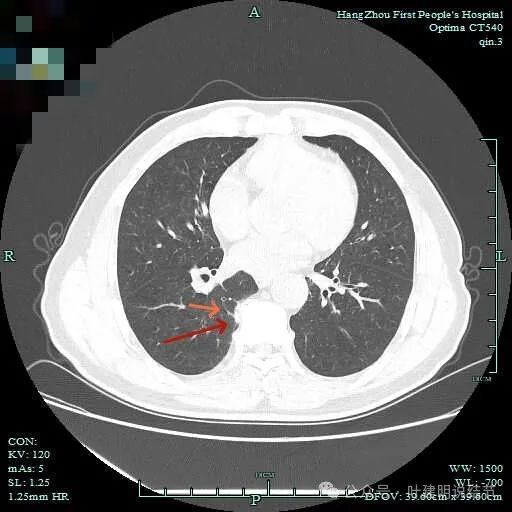

次病灶连续层面观察:

此层显得更呈小片状了。

与脊柱间似乎有间隙在,另见微小血管进入这条索状的偏高密度影处。

有细小血管进入,但说不上异常增粗。病灶仍是小片状,条状。

磨玻璃成分密度淡且界欠清,整体就是条索状弯曲的。

上图见细毛刺明显。

病灶实性伴细毛刺,与脊柱间有间隙在。